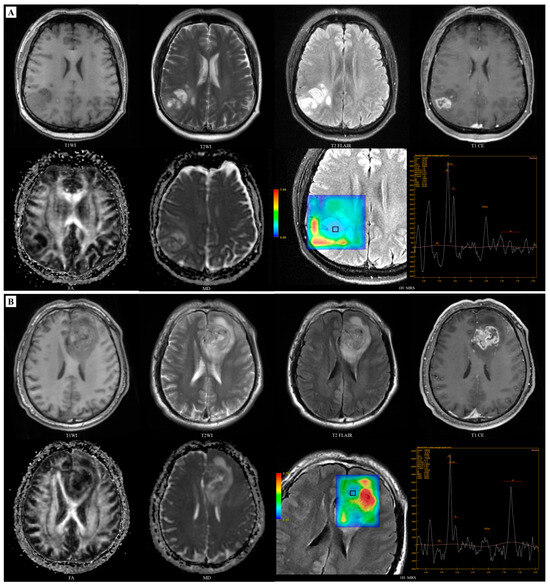

3.2. Models Development for Predicting IDH

3.3. Models Development for Predicting MGMT